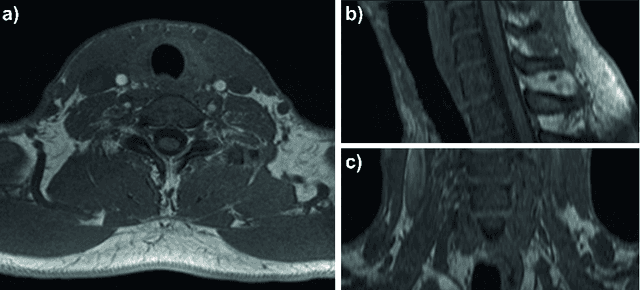

Abstract:Background: Thyroid volumetry is crucial in diagnosis, treatment and monitoring of thyroid diseases. However, conventional thyroid volumetry with 2D ultrasound is highly operator-dependent. This study compares 2D ultrasound and tracked 3D ultrasound with an automatic thyroid segmentation based on a deep neural network regarding inter- and intraobserver variability, time and accuracy. Volume reference was MRI. Methods: 28 healthy volunteers were scanned with 2D and 3D ultrasound as well as by MRI. Three physicians (MD 1, 2, 3) with different levels of experience (6, 4 and 1 a) performed three 2D ultrasound and three tracked 3D ultrasound scans on each volunteer. In the 2D scans the thyroid lobe volumes were calculated with the ellipsoid formula. A convolutional deep neural network (CNN) segmented the 3D thyroid lobes automatically. On MRI (T1 VIBE sequence) the thyroid was manually segmented by an experienced medical doctor. Results: The CNN was trained to obtain a dice score of 0.94. The interobserver variability comparing two MDs showed mean differences for 2D and 3D respectively of 0.58 ml to 0.52 ml (MD1 vs. 2), -1.33 ml to -0.17 ml (MD1 vs. 3) and -1.89 ml to -0.70 ml (MD2 vs. 3). Paired samples t-tests showed significant differences in two comparisons for 2D and none for 3D. Intraobsever variability was similar for 2D and 3D ultrasound. Comparison of ultrasound volumes and MRI volumes by paired samples t-tests showed a significant difference for the 2D volumetry of all MDs, and no significant difference for 3D ultrasound. Acquisition time was significantly shorter for 3D ultrasound. Conclusion: Tracked 3D ultrasound combined with a CNN segmentation significantly reduces interobserver variability in thyroid volumetry and increases the accuracy of the measurements with shorter acquisition times.